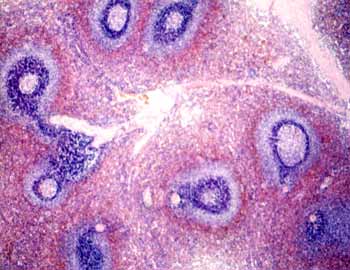

IX-2 Amígdala palatina (Hematoxilina-eosina) |

Visión

general: Se aprecia en superficie y en las criptas amigdalares

el revestimiento epitelial pluriestratificado pavimentoso no queratinizado

característico. A nivel subyacente destaca el tejido linfoide

difuso y nodular con predominio de los folículos o nódulos

secundarios.

específica: El tejido linfoide difuso, que se encuentra

en íntima relación con el epitelio y rodeando los nódulos

linfoides, está constituido fundamentalmente por linfocitos de

pequeño tamaño y plasmocitos. Los linfocitos están

en intima relación con las células epiteliales de las

criptas llegando a verse infiltradas por ellos en sus zonas más

profundas. Los nódulos linfoides secundarios presentan una cubierta

celular densa oscura constituida por los linfocitos de pequeño

tamaño que configuran el manto o casquete y un centro claro con

población celular heterogénea destacando celulas grandes

centroblásticas junto con células de menor tamaño

de núcleo hendido de tipo centrocítico de la estirpe linfocitaria.